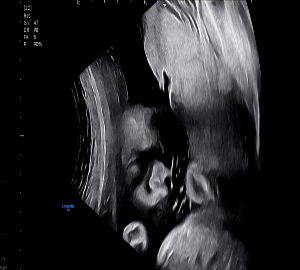

찹쌀이는 여전히 잘 자라고 있었다. 작은 몸짓 하나에도 힘이 느껴졌다.

KakaoTalk_20250914_213939247_01.jpg 26주차 빼꼼 얼굴을 내보이는 찹쌀이